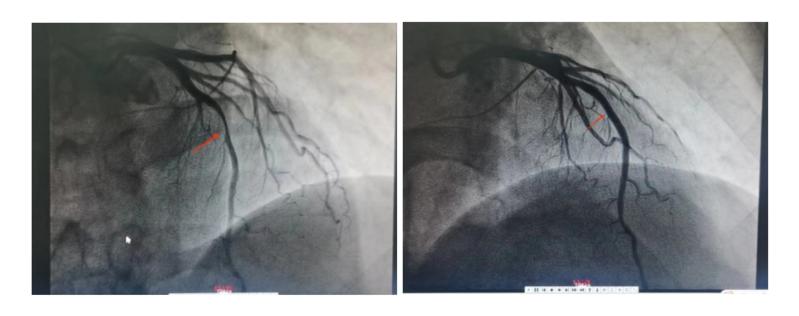

5月14日清晨,56岁患者李叔因突发胸痛被紧急送往广医五院心血管内科治疗。通过术前冠脉造影显示,李叔前降支(LAD)近段90%狭窄,属于严重狭窄级别,需进行冠脉内支架植入术,以防止李叔因心肌缺血导致心绞痛,甚至引起心肌梗死、心衰发生的风险。

李叔术前造影(左)和术后造影(右)